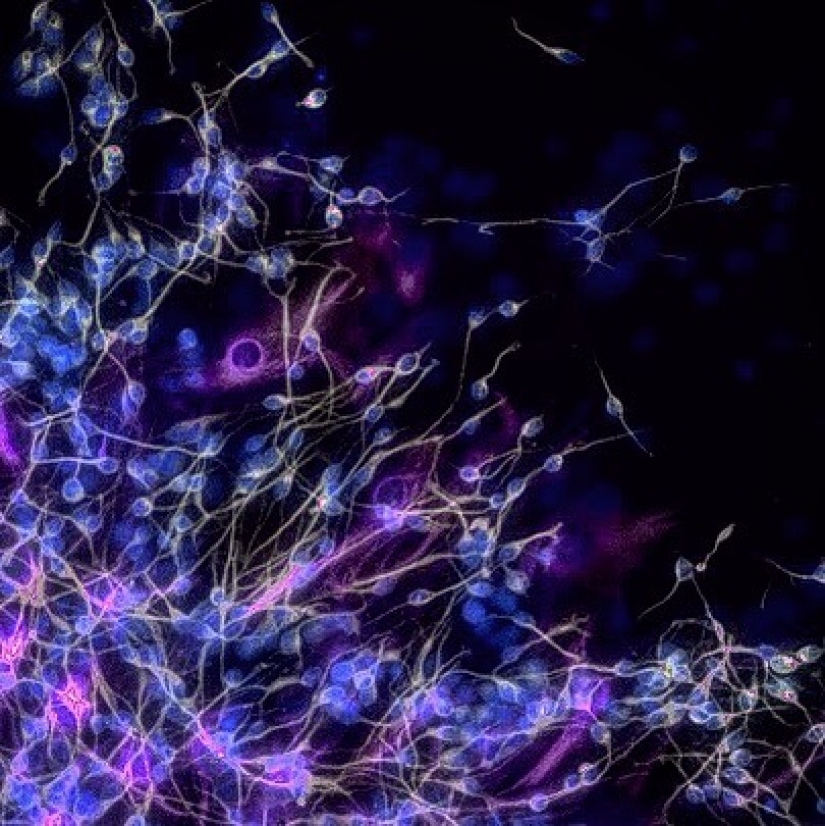

Imagínese, todos nuestros recuerdos son el producto de este grupo de células.